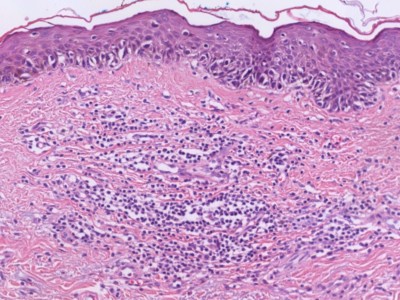

PA:Ook histologisch is het

superficial

spreading melanoom de meest voorkomende variant. Hierbij zijn de nesten van

atypische melanocyten gelegen in een band onder de epidermis. Er is

hoofdzakelijk groei in horizontale richting. Soms is er plaatselijk een

verticale groeifase, met invasie in de diepte of juist exofytische groei

zoals bij een

nodulair melanoom. Een andere veel voorkomende variant is het

in-situ melanoom, dat klinisch meestal beschreven wordt als lentigo maligna.

Kenmerken van maligniteit zijn melanocyten die opstijgen in de epidermis

(ascensie) of de dermis ingroeien, maar ook cellulaire kenmerken van de

melanocyten zelf (cytonucleaire atypie, kernpolymorfie, hyperchromatische

kernen, ruim helder tot eosinofiel cytoplasma, mitosefiguren). In het PA

verslag is de diepte van invasie belangrijk. Dit kan worden beschreven

t.o.v. de huidlagen (Clark levels), maar het is gebruikelijk om het te meten

in mm vanaf de epidermis (Breslow-dikte). Verder is het belangrijk of er epidermale ulceratie

is. Andere kenmerken die de patholoog kan beschrijven is (lymf) angio-invasie,

aanwezigheid / aantal dermale mitosefiguren, perineurale groei, lymfocytaire afweer respons, regressie, microsatellitose.